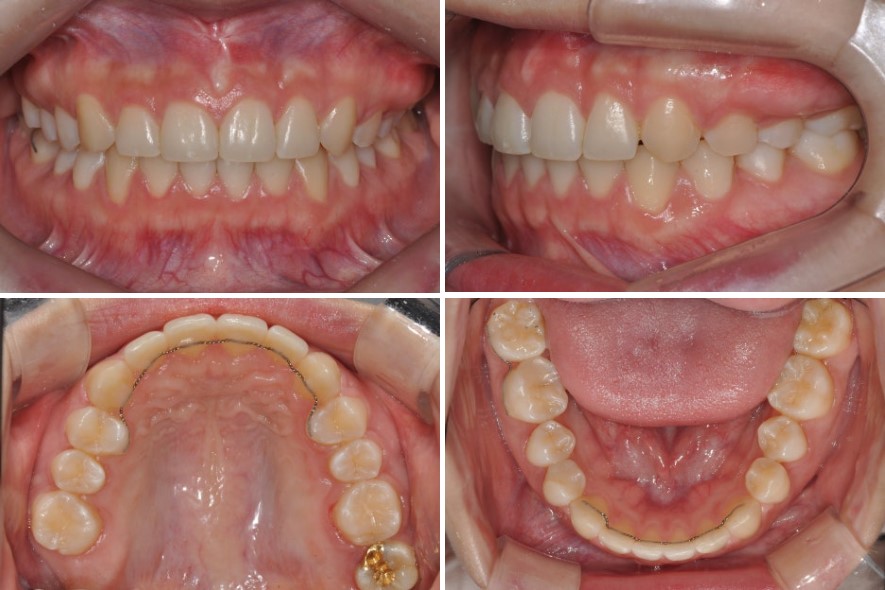

치료 경과와 결과: 비발치로도 가능한 의미 있는 변화

약 1년 11개월에 걸친 교정치료 끝에, 거미스마일 비발치 치료를 마무리했습니다.

먼저 구강 내 모습을 보면, 전체적인 교합이 적절하게 형성되었고,

오른쪽 위 어금니가 없는 공간으로 아래 어금니가 과도하게 올라오지 않도록 고정까지 해 둔 상태였습니다.

위·아래 어금니의 맞물림과 앞니 교합도 기능적으로 안정적인 상태로 정리되었습니다.

얼굴 모습만 놓고 보면, 입술을 다문 상태에서는 치료 전과 비교해 큰 변화는 없었습니다.

원래 입을 다물었을 때 크게 돌출된 인상이 아니었기 때문에, 자연스러운 결과라고 볼 수 있습니다.

하지만 웃는 모습을 비교해 보면 차이가 분명합니다.

아랫입술선과 조화를 이루는 보다 부드러운 스마일라인이 형성되었고,

치아 각도가 적절하게 회복되면서 윗입술이 위로 말려 올라가는 양상에도 변화가 생겨,

웃을 때 보이는 윗입술의 형태와 잇몸 노출이 함께 개선되었습니다.

엑스레이를 통해 치아 이동을 확인해 보면, 윗니 전체가 후방으로 꽤 많이 이동한 것을 볼 수 있습니다.

비발치 치료임에도 후방 이동량이 많았기 때문에, 치료 기간은 다소 긴 편이었지만,

환자분께서 잘 협조해 주신 덕분에 원하는 방향으로 좋은 결과를 얻을 수 있었습니다.